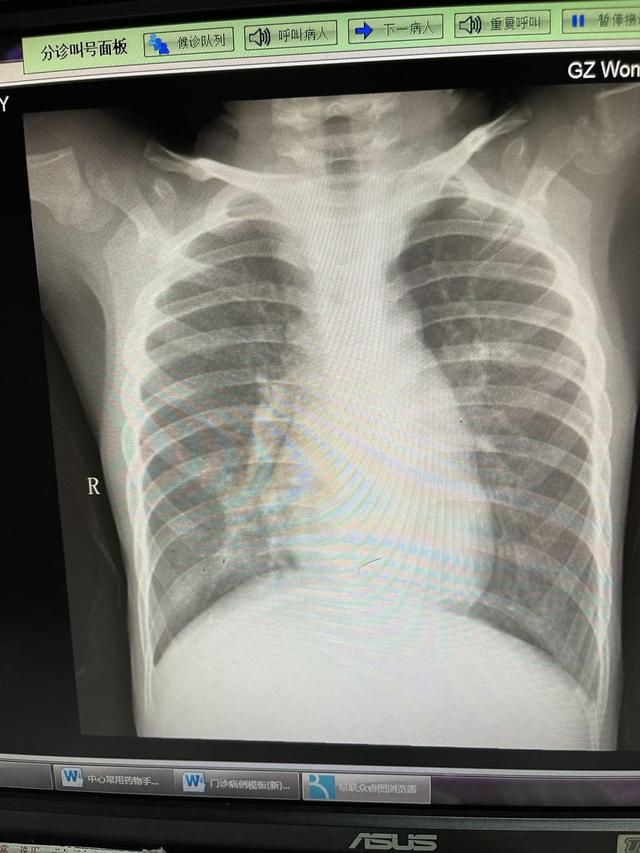

但定睛一看典型结果:支气管肺炎,如下图所示是什么:

不由得心中一紧。

医生拿到肺炎片子,留出一丝为难的神色,说道:“肺炎,这个需要输液治疗。不过呢,现在市妇幼只能留观,观察一个晚上,然后第二天也不能住院,要去人民路院区住院,早点过去应该能排上队”。